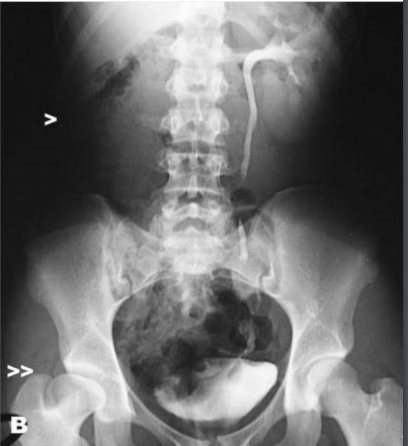

What is this lesion and why are the kidneys susceptable ?

Kidney Infarction

The kidneys are susceptable

1. Arterial blood supply to the cortex is terminal

- few anastomoses of the renal blood vessels

2. Receives a large portion of overall blood volume 25%